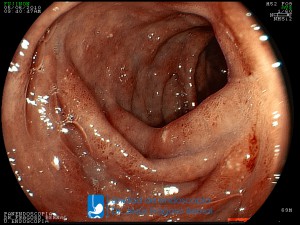

La Unidad de Endoscopía fue creada en 2002 por el Dr. Jesús Fragoso Bernal, es pionera en el estado por la utilización de la tecnología más avanzada, que nos permite ofrecer servicios integrales de diagnóstico y tratamiento para las enfermedades del aparato digestivo.

"La Unidad de Endoscopía se ha caracterizado por un progreso continuo desde su inicio marcando la pauta en los procedimientos endoscópicos en el estado de Tlaxcala y estando siempre a la vanguardia tecnológica."